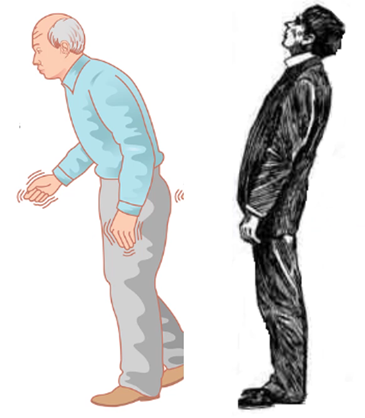

- Kardinalsymptom

- Tremor (vilo-)

- Rigiditet (tonusökning)

- Hypokinesi (rörelsearmod)

- Associerade symptom

- Störd jämviktskontroll

- Förlust av posturala reflexer

När kan detta ses?

Parkinsons

- Vid Parkinson risk för fall framåt, Parkinson plus risk för fall bakåt